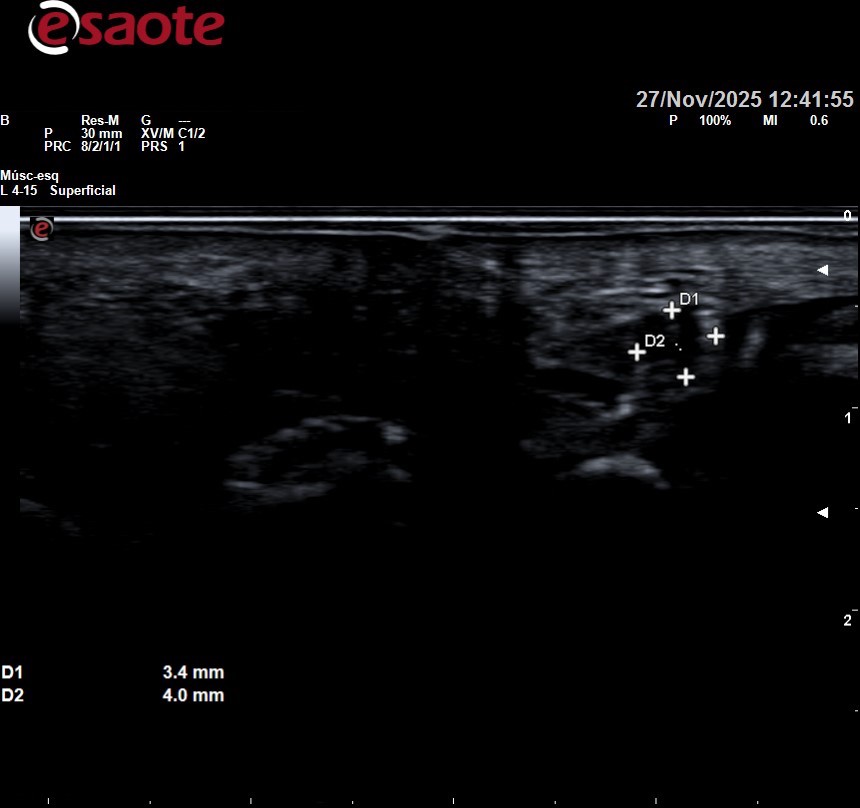

Imagenes ecográficas normales y de un neuroma de morton

Se puede observar arriba la ecografía de una paciente con neuroma de morton entre tercer y cuarto metatarsiano sintomatológico, que posteriormente se infiltró. Se observa como desde lo metatarsianos hacia los dedos el nervio se va haciendo más gordo. En la foto de abajo a la derecha lo vemos a lo largo en esa zona negra circular que se observa de la mitad de la imagen hacia la izquierda.